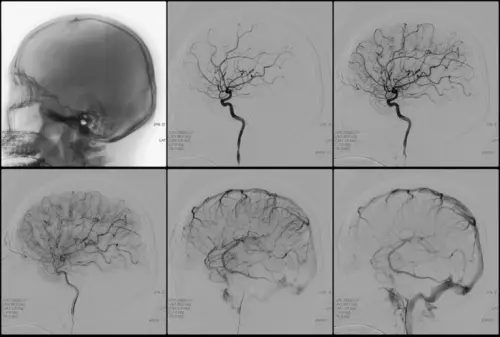

Пример УЗИ головы и шеи. Демонстрация процесса сканирования в реальном времени.